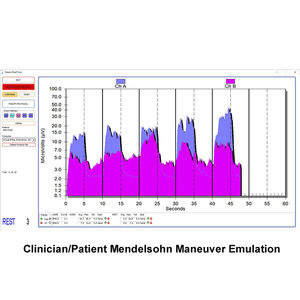

... SOFTWARE TELESIS® PARA LA SERIE PATHWAY® MR Incluye una unidad flash USB del software Telesis® para la serie Pathway® MR, un cable de interfaz serie USB, una guía del operador del software Telesis® para ...

... SOFTWARE TELESIS® ST PARA LA SERIE PATHWAY® MR Incluye una unidad flash USB del software Telesis® para la serie Pathway® MR, un cable de interfaz serie USB, una guía del operador del software Telesis® ...